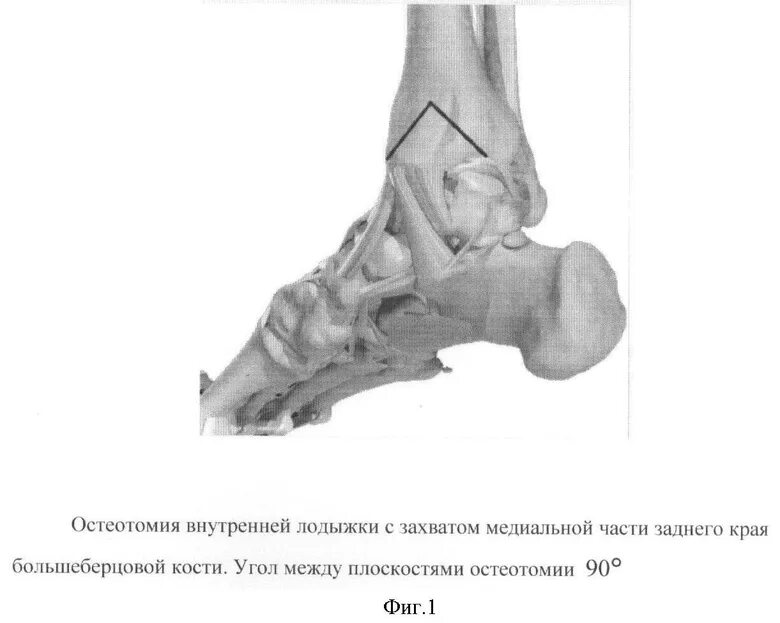

Пяточная остеотомия